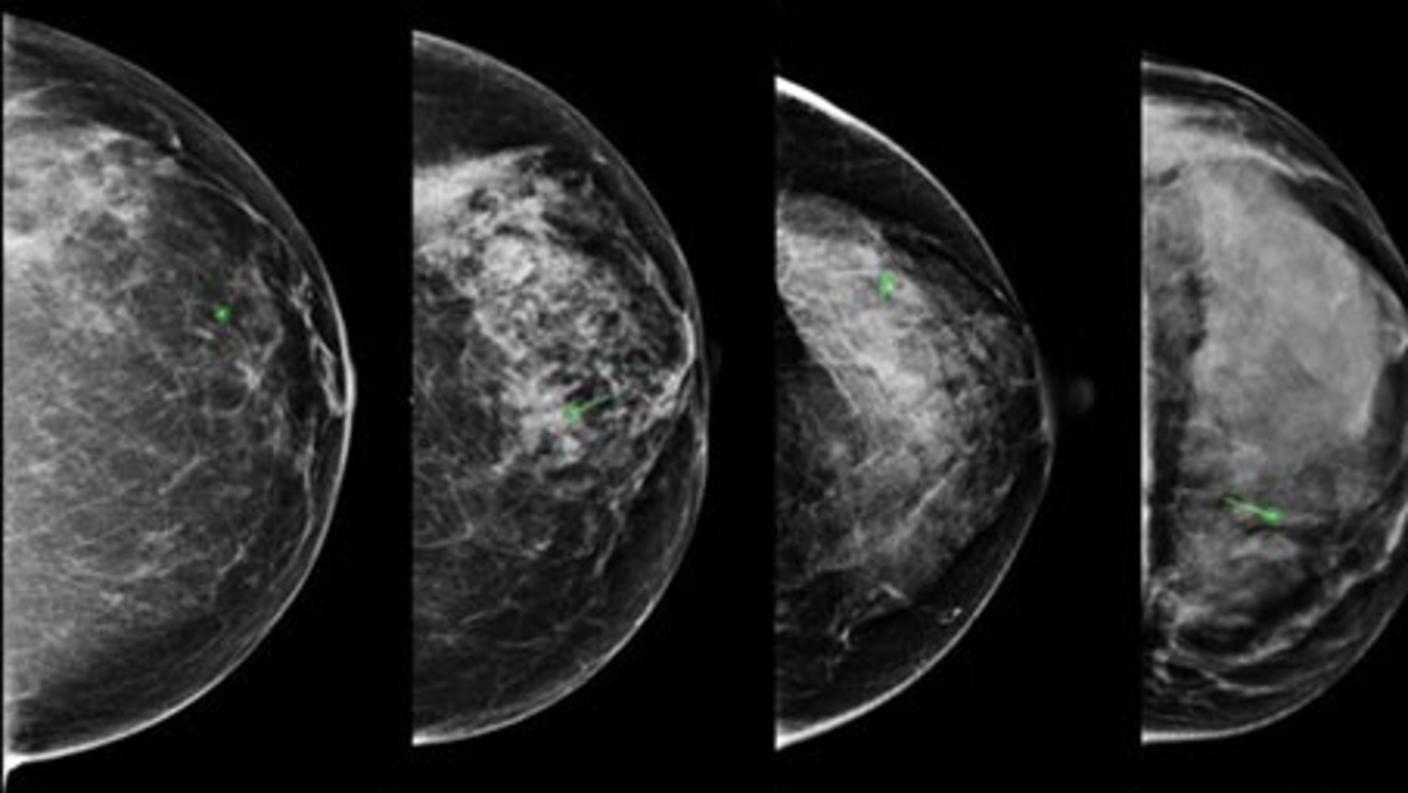

Ultrasound tomography (UST) is a novel radiological method that provides a three-dimensional image of the breast. Collaborators at Karmanos Cancer Institute have developed a UST device that allows the calculation of sound speed, an objective physical measurement that is positively correlated with breast density. Thus, UST offers the possibility of determining breast density serially over time as a volume, without compression of the breast or exposure to potentially harmful ionizing radiation.

Investigators enrolled women receiving tamoxifen for atypical lobular or ductal hyperplasia, lobular or ductal carcinoma in situ, or invasive breast cancer at Karmanos Cancer Institute to undergo repeated volumetric breast density assessment with UST. Investigators are assessing whether UST examinations performed as early as 1-3 months following initiation of tamoxifen can identify women whose breast density is demonstrated to have declined at one year using mammography. For comparison, they enrolled age-, race-, and menopausal status-matched women without breast cancer to assess changes in UST density over time without tamoxifen exposure. Risk factor data and blood were collected from participants. The broader study objective is to assess the concept of breast density as a biosensor of tamoxifen response and UST as a useful tool for making this determination.

They found ultrasound tomography sound speed estimates to be highly reproducible surrogate measures of volumetric breast density. These results will inform the development of methods for serial assessment of density, an important area for future investigation as density changes may translate into changes in breast cancer risk.